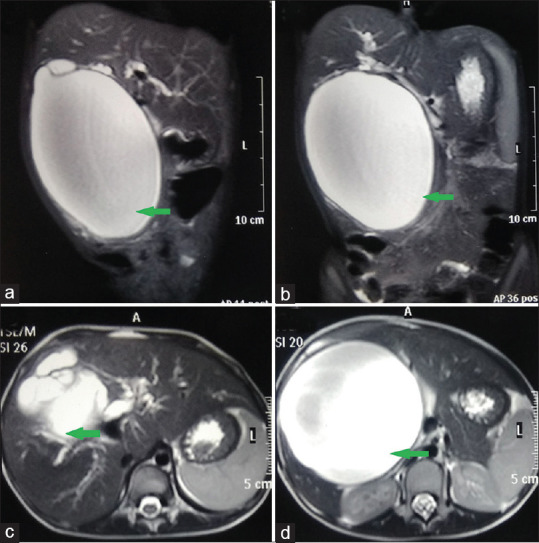

Results: A total of 74 patients were included in this study. There were 59 (79.73%) females and 15 (20.27%) males. Thirty-nine (52.70%) patients had jaundice at the time of presentation. Magnetic resonance cholangiopancreatography was performed in 57 (77.03%) patients following ultrasonography. Intraoperatively, malrotation was present in 2 (2.70%) patients. In our study, operating time ranged from 60 to 195 min (mean: 118 min). Hospital stays ranged from 8 to 17 days (mean: 11.5 days). The post-operative biliary leak was seen in 7 (9.50%) patients, out of which 6 (8.11%) minor leaks were managed conservatively. Roux-en-Y HJ was performed on 1 (1.35%) patient with a major leak. In our series, 4 (5.40%) patients developed cholangitis; post-operative haemorrhagic nasogastric aspirate 5 (6.76%), post-operative pancreatitis 3 (4.05%) and wound infection 4 (5.40%) were observed and managed conservatively. None of the patients in our study developed an anastomotic stricture, bile gastritis and adhesive small bowel obstruction.